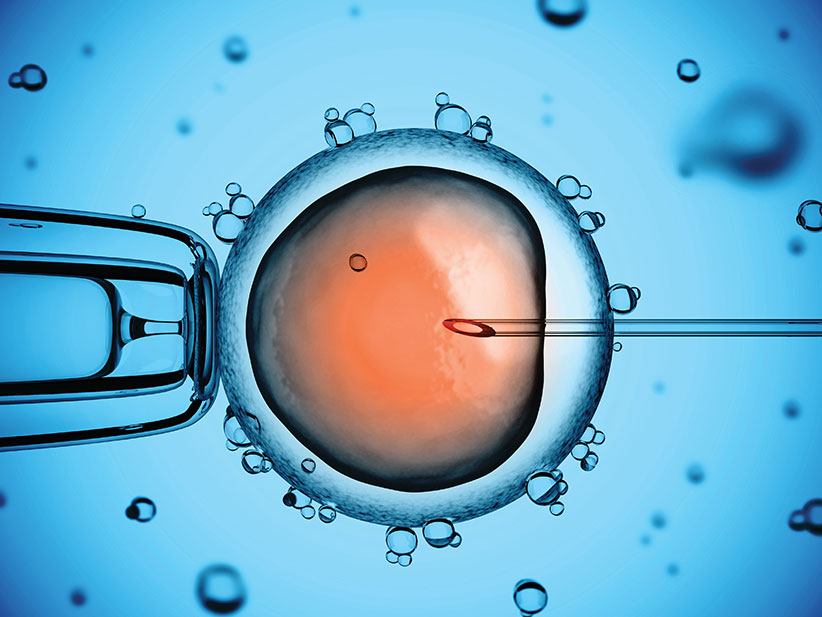

Това е процес, при който яйцеклетка е отделена от яйчника на майката, оплодена със сперматозоиди на бащата в лабораторни условия и върната в матката на майката.

Едуардс има успехи в оплождането в лабораторни условия, а Стептоу разработва метод за извличане на яйцеклетки от яйчниците.

Техниката за директно инжектиране на сперматозоид в яйцеклетката, разработена в края на 80те, е пробив в лечението на мъжкия стерилитет.

Интрацитоплазмена спермална инжекция (ИКСИ)